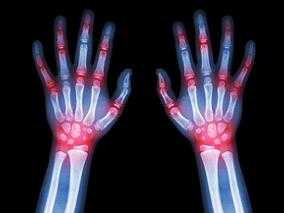

依那西普治疗类风湿性关节炎 老年患者安全性和有效…

1小时条评论老年人受类风湿性关节炎(RA)的影响尤其严重,但很少有研究涉及该人群中治疗的有效性和安全性。2019年9月,发表在《Drugs Aging》的一项研究,调查了老年RA患者使用依那西普的安全性和有效性。 目的:本研究的目的是评价依那西普在老年(年龄ge;65岁)RA患者中的有...

抗菌药物增加RA风险 或是由于…

1小时条评论有研究显示,抗菌药物诱导的人微生物群失调是慢性自身免疫疾病进展的起因。2019年8月,发表在《BMC Med》的一项巢式病例对照研究,调查了抗菌药物使用与类风湿性关节炎(RA)发病之间的相关性。 目的:本研究的目的是,评价抗菌药物使用是否与RA发病相关。 方法:...